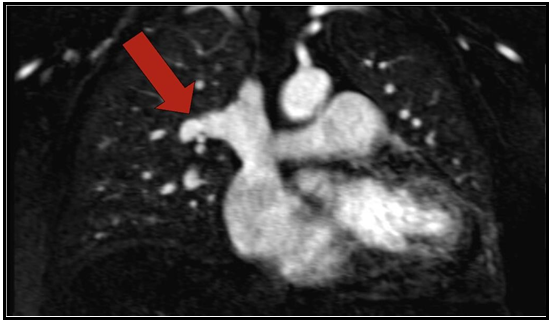

Case Study: Partial Anomalous Pulmonary Venous Return Of The Right Upper Pulmonary Vein Into The Cephalic Portion Of The SVC Causing A Left-To-Right Shunt In 56-Year-Old Asian Female